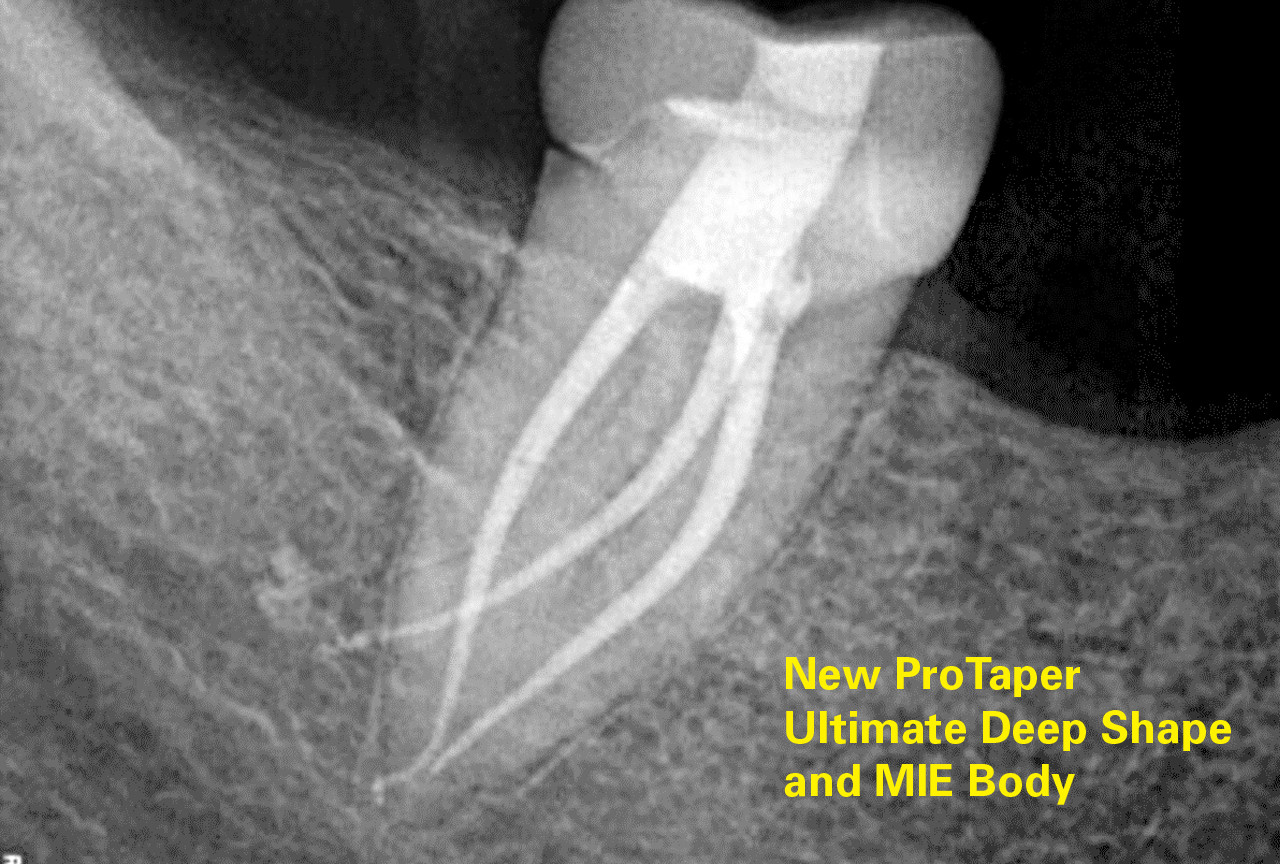

Pierre Machtou, John West and Clifford J Ruddle discuss the significance, rationale and benefit of deep shape in endodontics.